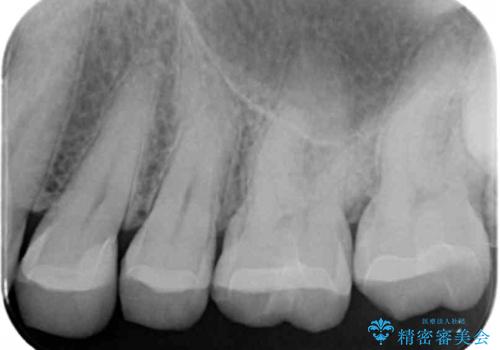

笑った時にチラついていた銀歯がなくなり大変喜んでいただけました。

セラミックは樹脂よりも変色しにくいため見た目が気になる方には特におすすめです。

この方は詰め物が割れてしまうのを防ぐためにナイトガードも作成しました。

- かみ合わせや歯ぎしりが強すぎる方はセラミックが割れてしまう可能性があります